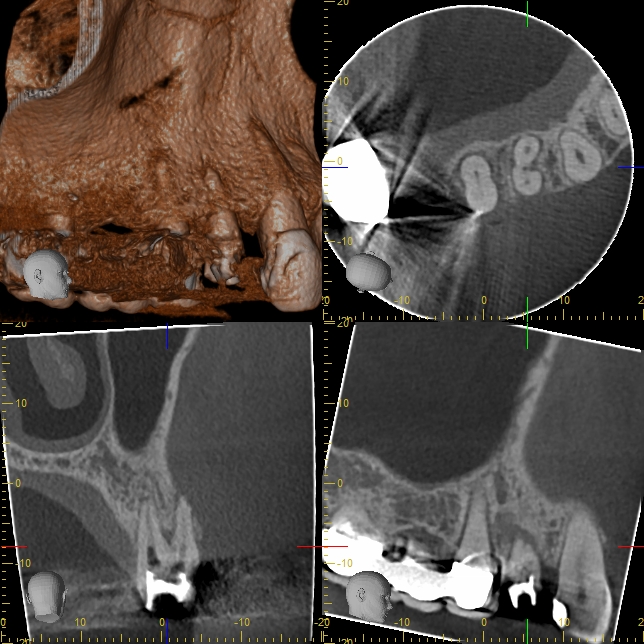

XYZView_20180115_113820 Veröffentlicht 1. Februar 2018 am 644 × 644 in Immer schön skeptisch bleiben 3